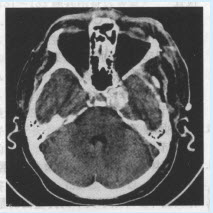

患者,男,45岁。头痛半年,CT检查如下图。

第1题,共4个问题

(单选题)该患者最有可能的诊断为()

A:脑膜瘤

B:垂体瘤

C:动脉瘤

D:星形细胞瘤

E:AVM

F:以上都不是

第2题,共4个问题

(单选题)最需与本病鉴别的肿瘤为()

C:胶质瘤

D:神经源性肿瘤

E:转移瘤

第3题,共4个问题

(单选题)进一步检查,最佳的检查方法是()

A:MRI

B:MRA

C:增强扫描

D:DSA

E:手术切开

第4题,共4个问题

(多选题)该病按病因分类可分为()

A:先天性

B:外伤性

C:感染性

D:动脉硬化性

E:原发性

F:假性